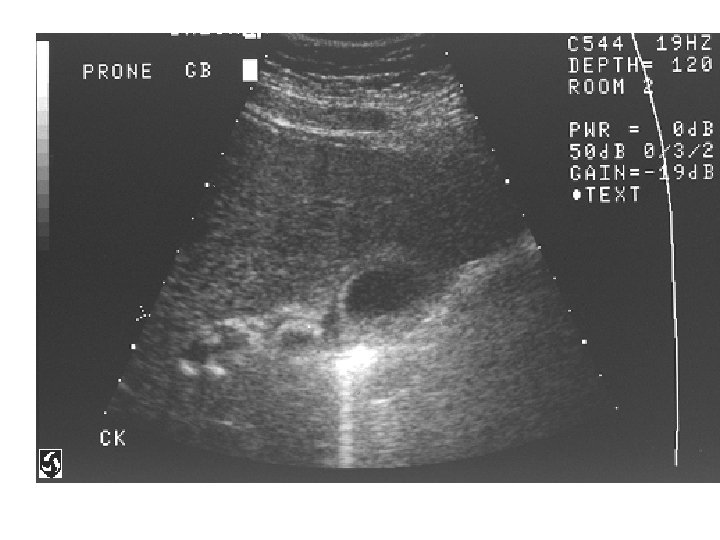

Normal Gallbladder

Gallbladder Stones